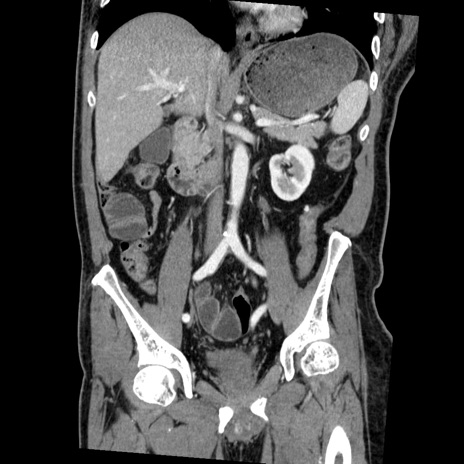

症例22(冠状断像)

【症例】50歳代男性

【主訴】腹痛

【現病歴】AVMからの被殻出血のため回復期リハ病棟入院中。 本日午後3時頃急に下腹部痛が出現した。

【既往歴】AVM、被殻出血、虫垂炎、高血圧

【身体所見】意識晴明、左半身不全麻痺、会話の理解は良好、36.5°C、腹部:膨隆、全体に板状硬、下腹部正中に圧痛点あり、反跳痛-、筋性防御不明、右下腹部にope scar

【データ】WBC 9400、CRP 0.06